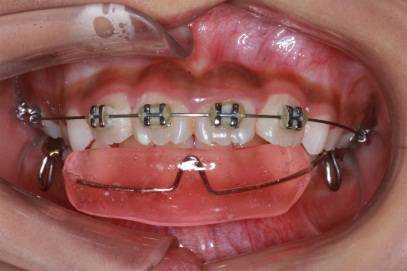

唇侧矫治器根据不同材料,主要分为金属矫治器和陶瓷矫治器;根据弓丝安放方式,又可分为自锁和非自锁矫治器两大类。金属非自锁矫治器最普通,每颗牙都需要通过结扎丝来固定弓丝,较显眼;而陶瓷非自锁矫治器较金属更为美观,但也需要结扎丝结扎;金属自锁矫治器可以通过矫治器上的“盖子”锁住弓丝,不需要结扎丝结扎,因而更舒适,医生操作更简便,排齐速度也略快;陶瓷自锁矫治器则较为美观,且不需要结扎丝结扎来固定弓丝,同时满足美观、舒适的特点。

(摘自“第三章第三节 牙套的选择”)

金属非自锁矫治器(左)与陶瓷非自锁矫治器(右)

金属自锁矫治器(左)与陶瓷自锁矫治器(右)